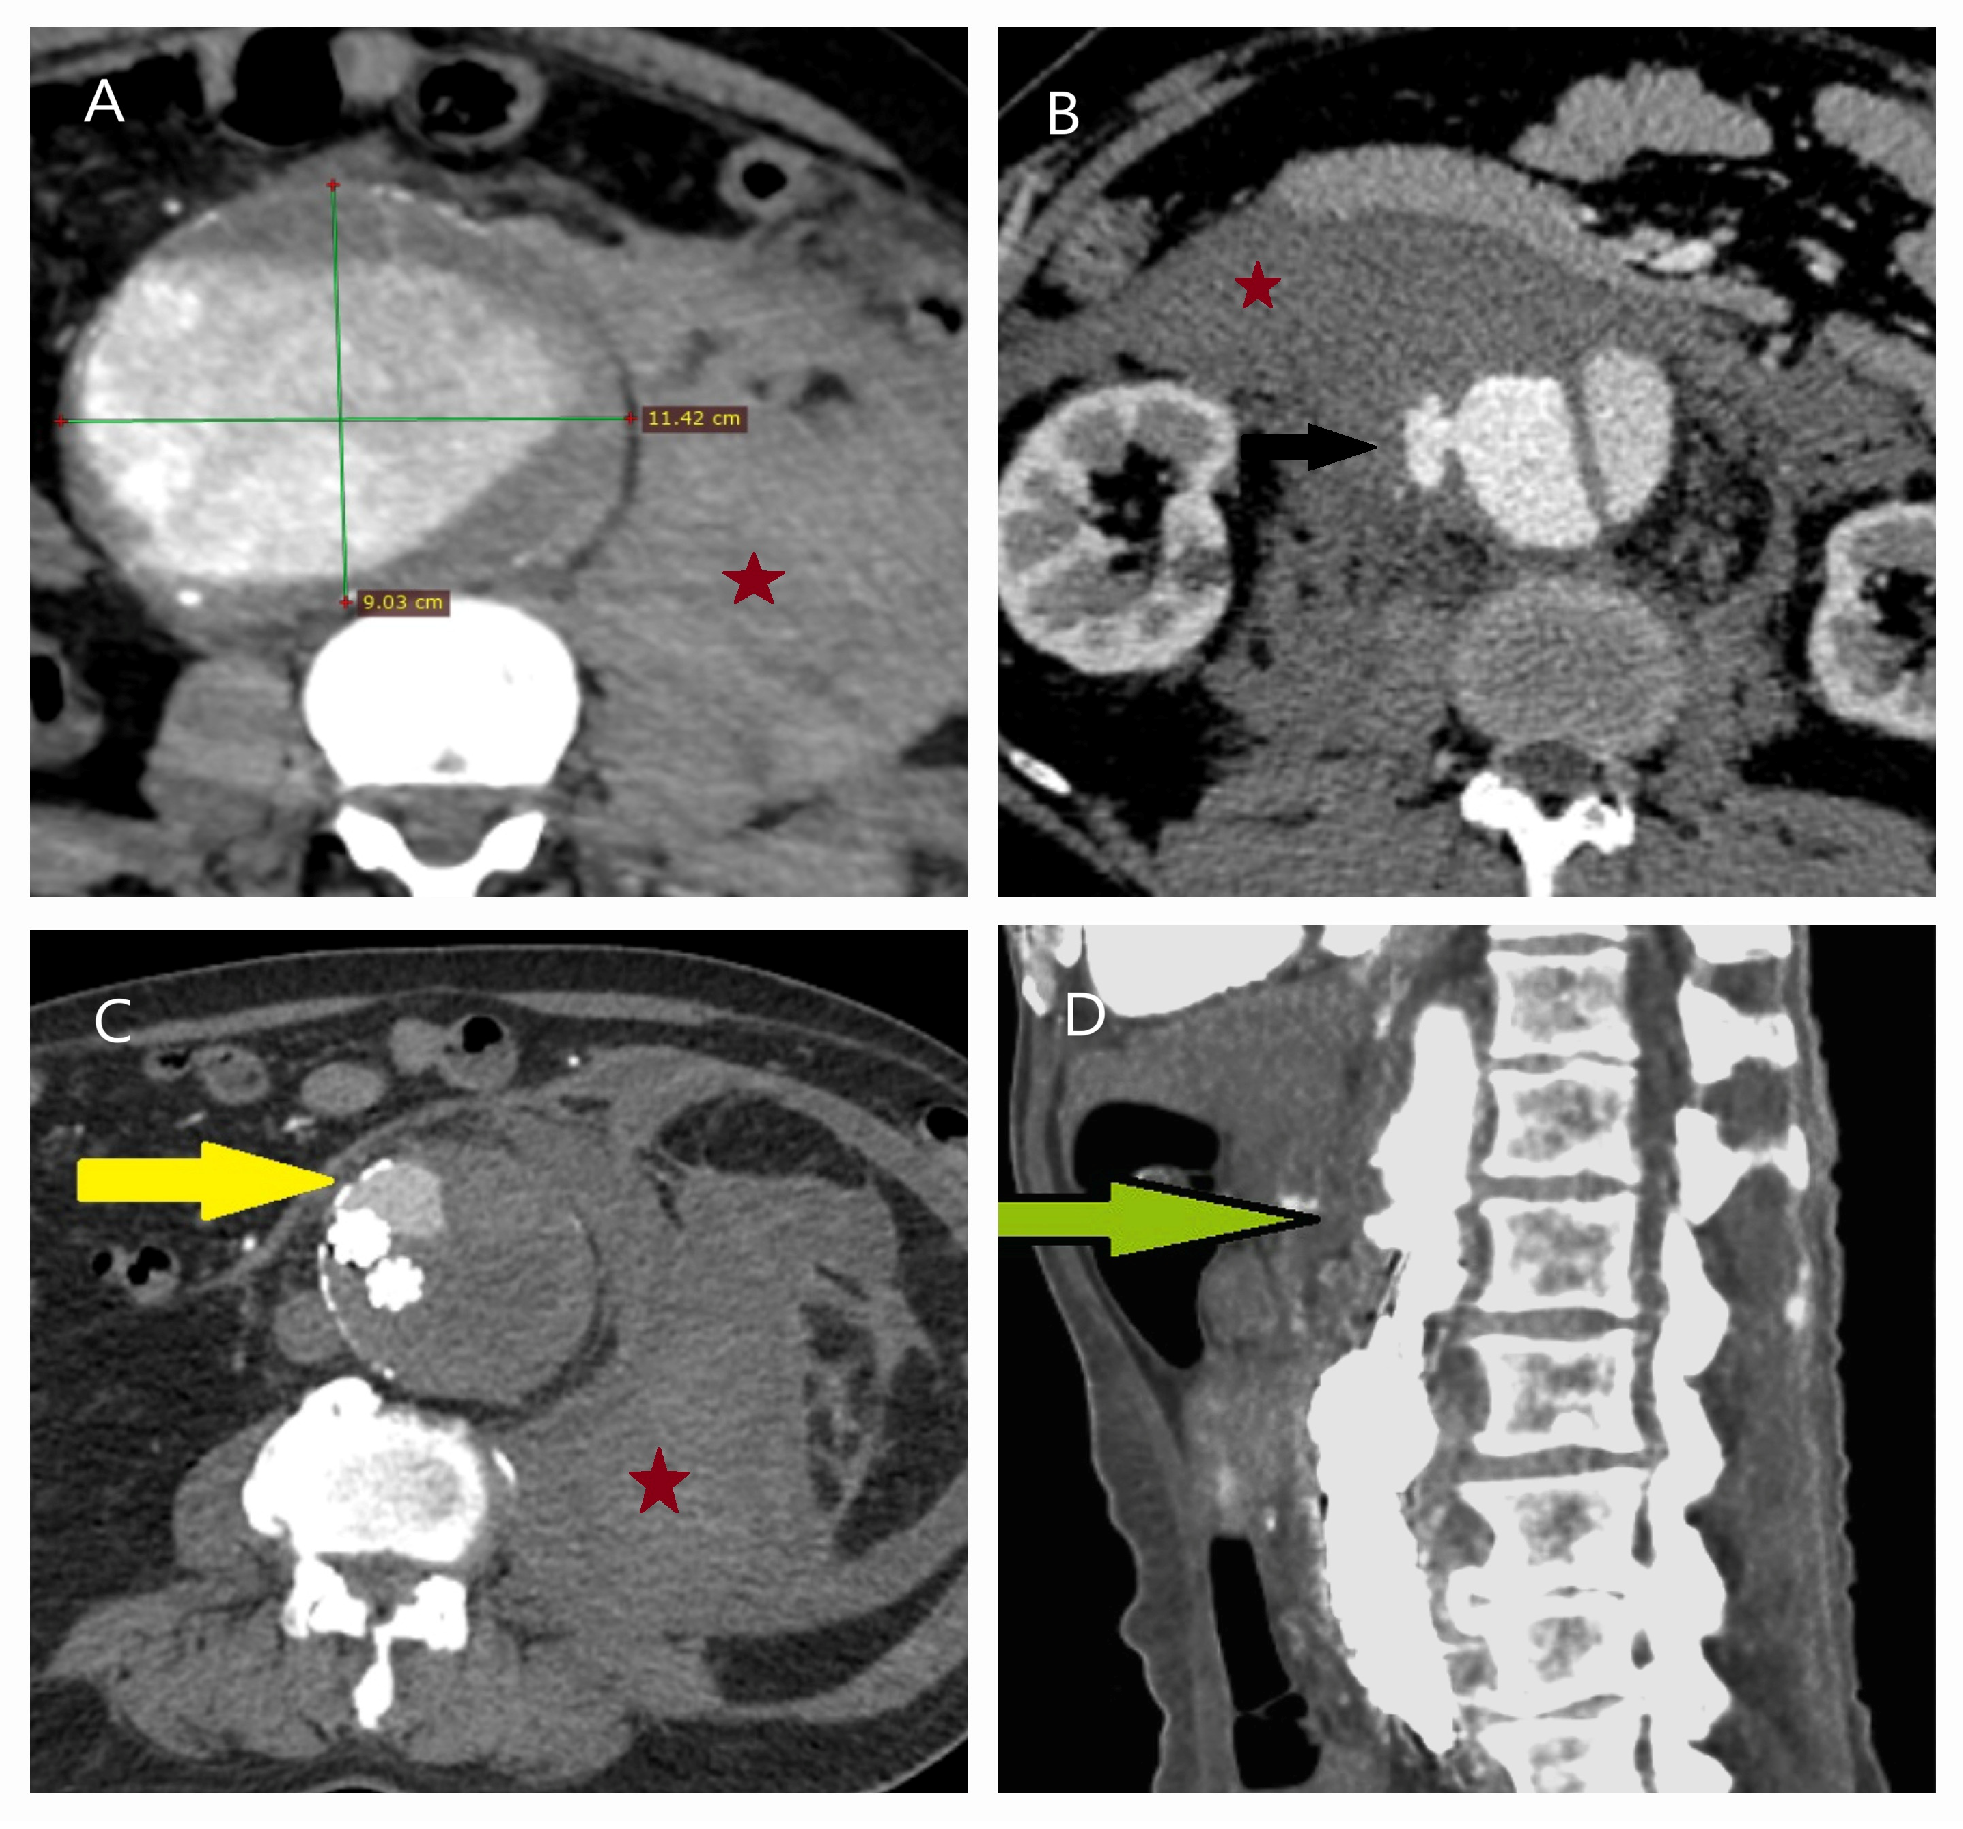

5.1. Failure of EVAR

5.2. Conversion to Open Surgery